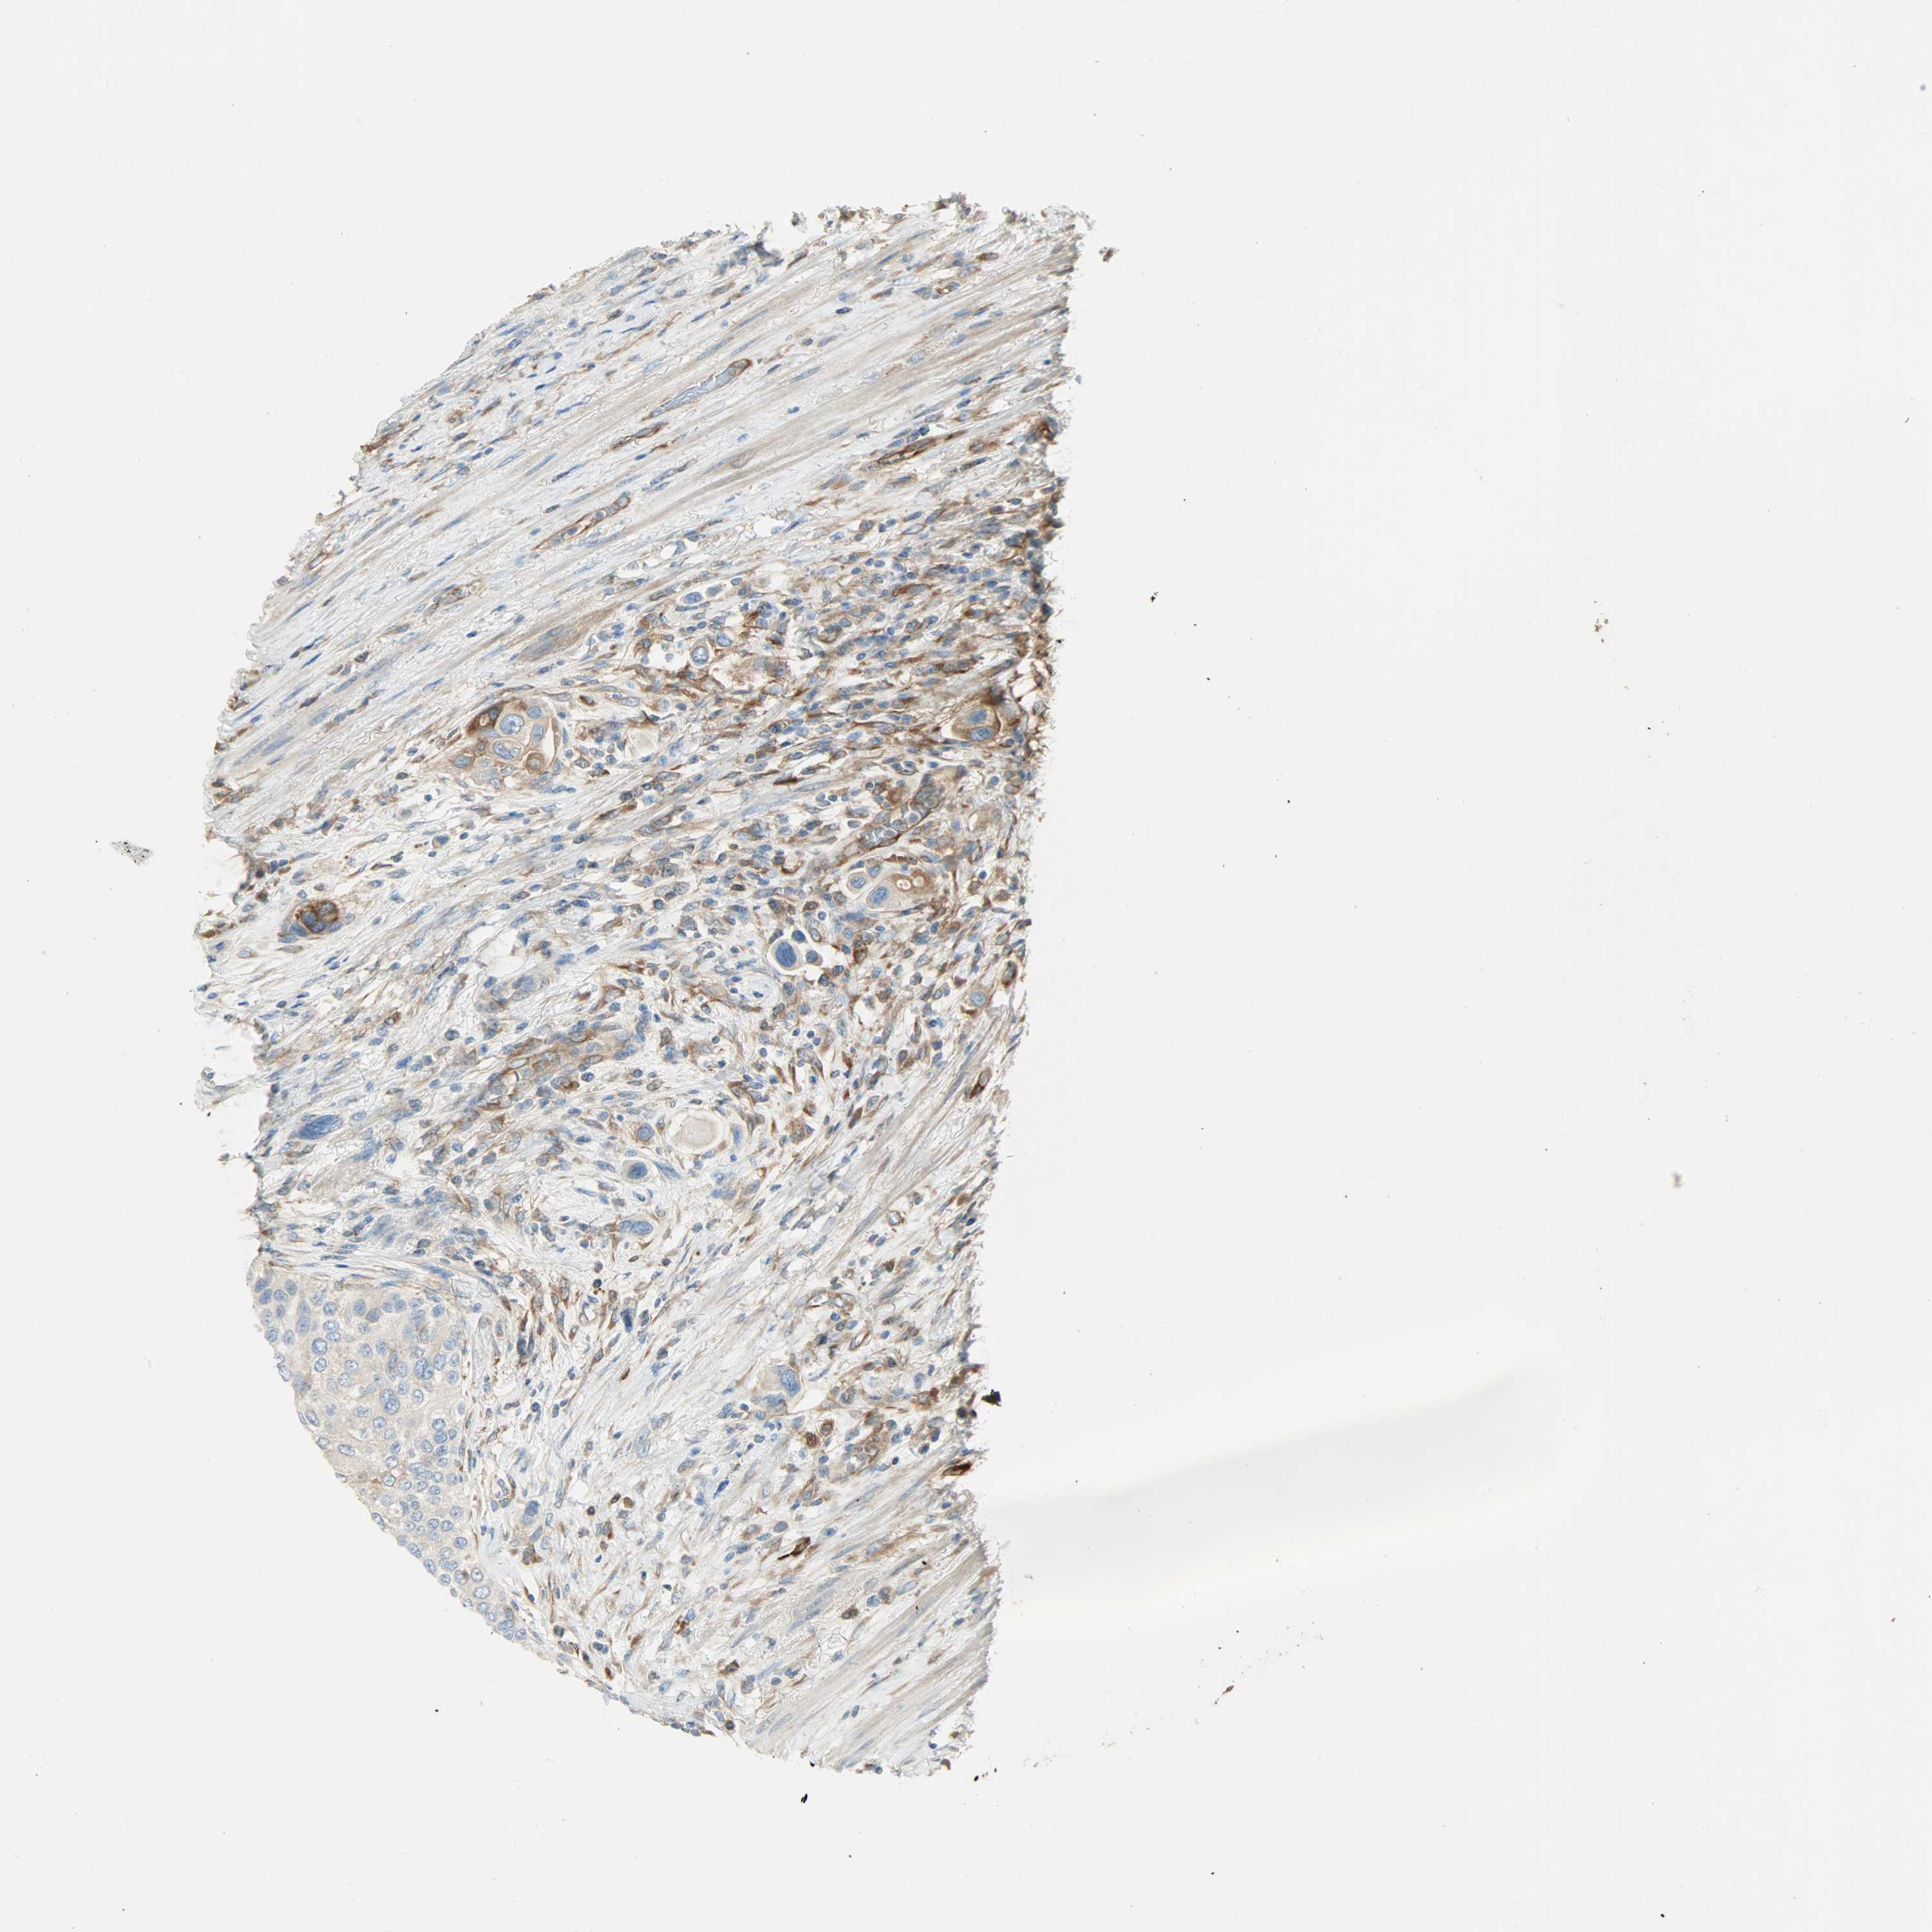

UROTHELIAL CANCER - Protein expressioni

A mouse-over function shows sample information and annotation data. Click on an image to view it in a full screen mode. Samples can be filtered based on level of antibody staining by selecting one or several of the following categories: high, medium, low and not detected. The assay and annotation is described here.

Note that samples used for immunohistochemistry by the Human Protein Atlas do not correspond to samples in the TCGA dataset.

Antibody stainingi

Antibody staining in the annotated cell types in the current human tissue is reported as not detected, low, medium, or high, based on conventional immunohistochemistry profiling in selected tissues. This score is based on the combination of the staining intensity and fraction of stained cells.

Each image is clickable and will lead to virtual microscopy that enables deeper exploration of all samples and also displays staining intensity scores, fraction scores and subcellular localization as well as patient and tissue information for each sample.

Antibody HPA005573

Staining

High

Medium

Low

Not detected

Intensity

Strong

Moderate

Weak

Negative

Quantity

>75%

75%-25%

<25%

None

Location

Nuclear

Cytoplasmic/membranous

Cytoplasmic/membranous,nuclear

Urothelial carcinoma, High grade

Urothelial carcinoma, Low grade